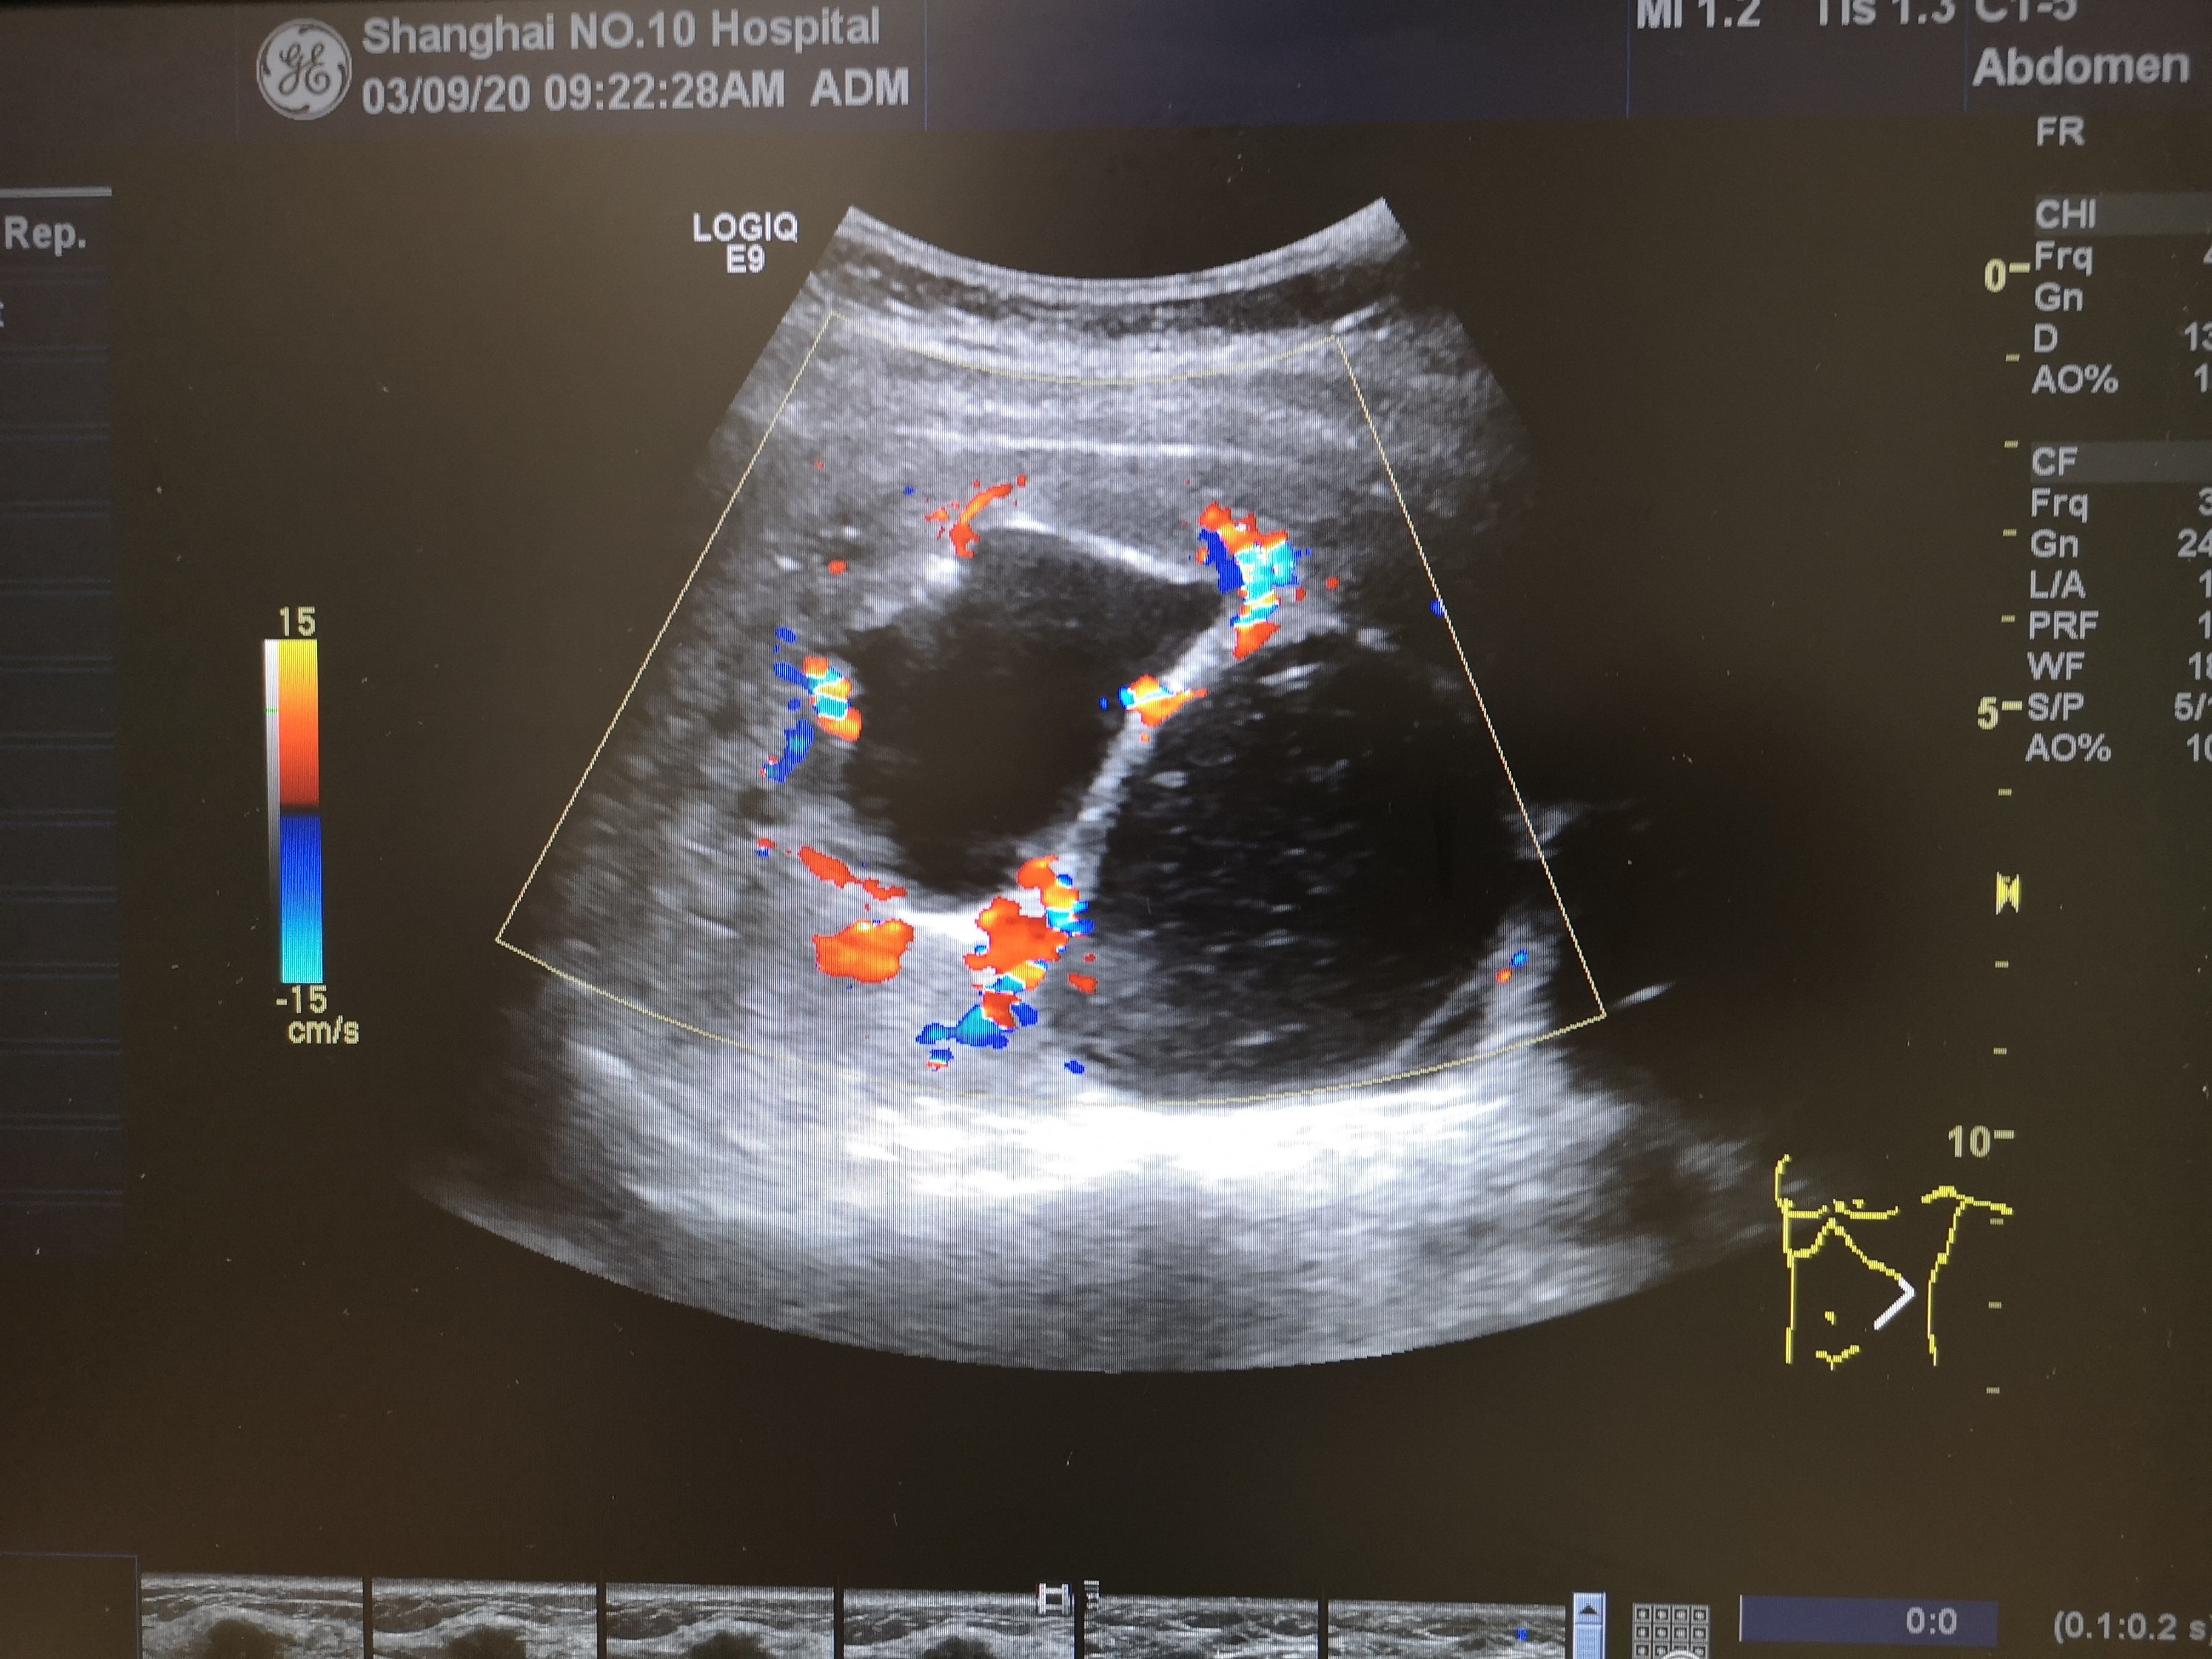

巨大积水肾 - 超声医学讨论版 - 爱爱医医学论坛

图片尺寸3264x1840